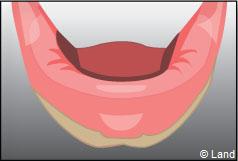

Exemple d’une réhabilitation complète implantaire

Situation clinique initiale